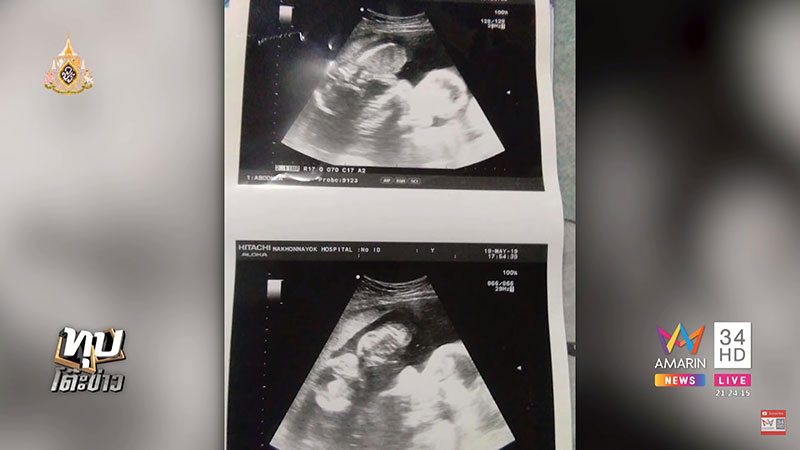

เกี่ยวกับเรื่องนี้ (26 พฤษภาคม 2562) รายการทุบโต๊ะข่าว ทางช่อง Amarin TV รายงานบทสัมภาษณ์ นางสาววลัยพร หรือ มาย อายุ 23 ปี เจ้าของโพสต์ เปิดเผยว่า ก่อนหน้านี้ตนปวดท้องหน่วง คือวันที่ 19 พฤษภาคม จึงได้ไปหาหมอ และได้รับการฉีดยากันแท้งให้ 1 เข็ม แล้วกลับบ้าน แต่เมื่อกลับมาบ้านน้ำคร่ำกลับแตกขณะอาบน้ำ จึงรีบไปโรงพยาบาล ตอนแรกพยาบาลแจ้งว่าเด็กยังอยู่ทั้งคู่ แต่หลังจากหมอมาตรวจปากมดลูก กลับบอกว่ายังไงก็แท้ง ให้นอนรอ ตนนอนรอจนเช้าก็ยังไม่คลอด ก่อนที่หมอจะมาบอกว่าเด็กเสียชีวิตไปแล้ว 1 คน ต้องเอาออกทั้งคู่ เพราะไม่อย่างนั้นแม่จะติดเชื้อแล้วเสียชีวิตด้วย ตอนนั้นตนได้ถามไปว่าเด็กเป็นผู้ชายหรือผู้หญิง หมอกลับตอบกลับว่า จะรู้ไปทำไม รู้ไปก็ไม่ได้เลี้ยง ทำให้ตนเสียใจมาก ถึงกับร้องไห้

นางสาววลัยพร กล่าวต่อว่า วันที่ 20 ตนตัดสินใจย้ายโรงพยาบาล ซึ่งเมื่อมาถึงศูนย์การแพทย์สมเด็จพระเทพรัตนราชสุดาฯ สยามบรมราชกุมารี หมอแจ้งว่า ลูกแฝดในท้องยังอยู่ แต่น้ำคร่ำแห้งหมดแล้ว อย่างไรก็ต้องเอาออก เพราะเด็กไม่สามารถเจริญเติบโตได้ แต่หมอก็ให้ตนทำใจก่อน เมื่อตัดสินใจจึงฉีดยาเร่งคลอด ผลปรากฏว่าเด็กตัวใหญ่เป็นเพศชายทั้งคู่ น้ำหนักคนละ 500 กรัม ร่างกายสมบูรณ์